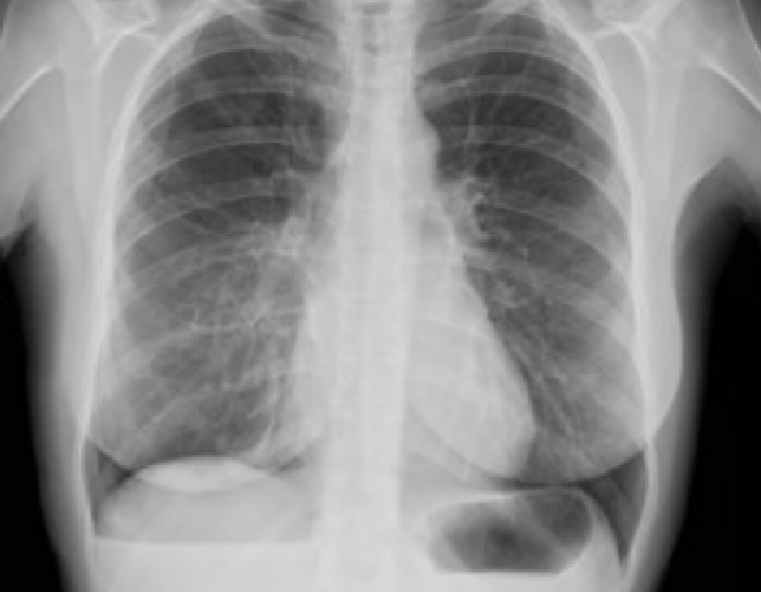

Catamenial Pneumothorax: A Challenging Diagnosis

Catamenial pneumothorax is the most frequent manifestation of thoracic endometriosis: this article is about a case in which the diagnosis was formulater only when a temporal connection with menstrual bleeding was noticed and when implementation of a specific medical treatment was able to prevent further recurrences of the desease.